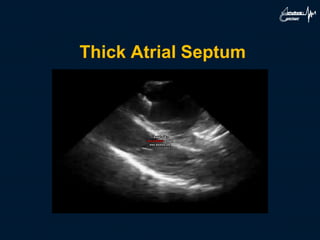

Thick Atrial Septum